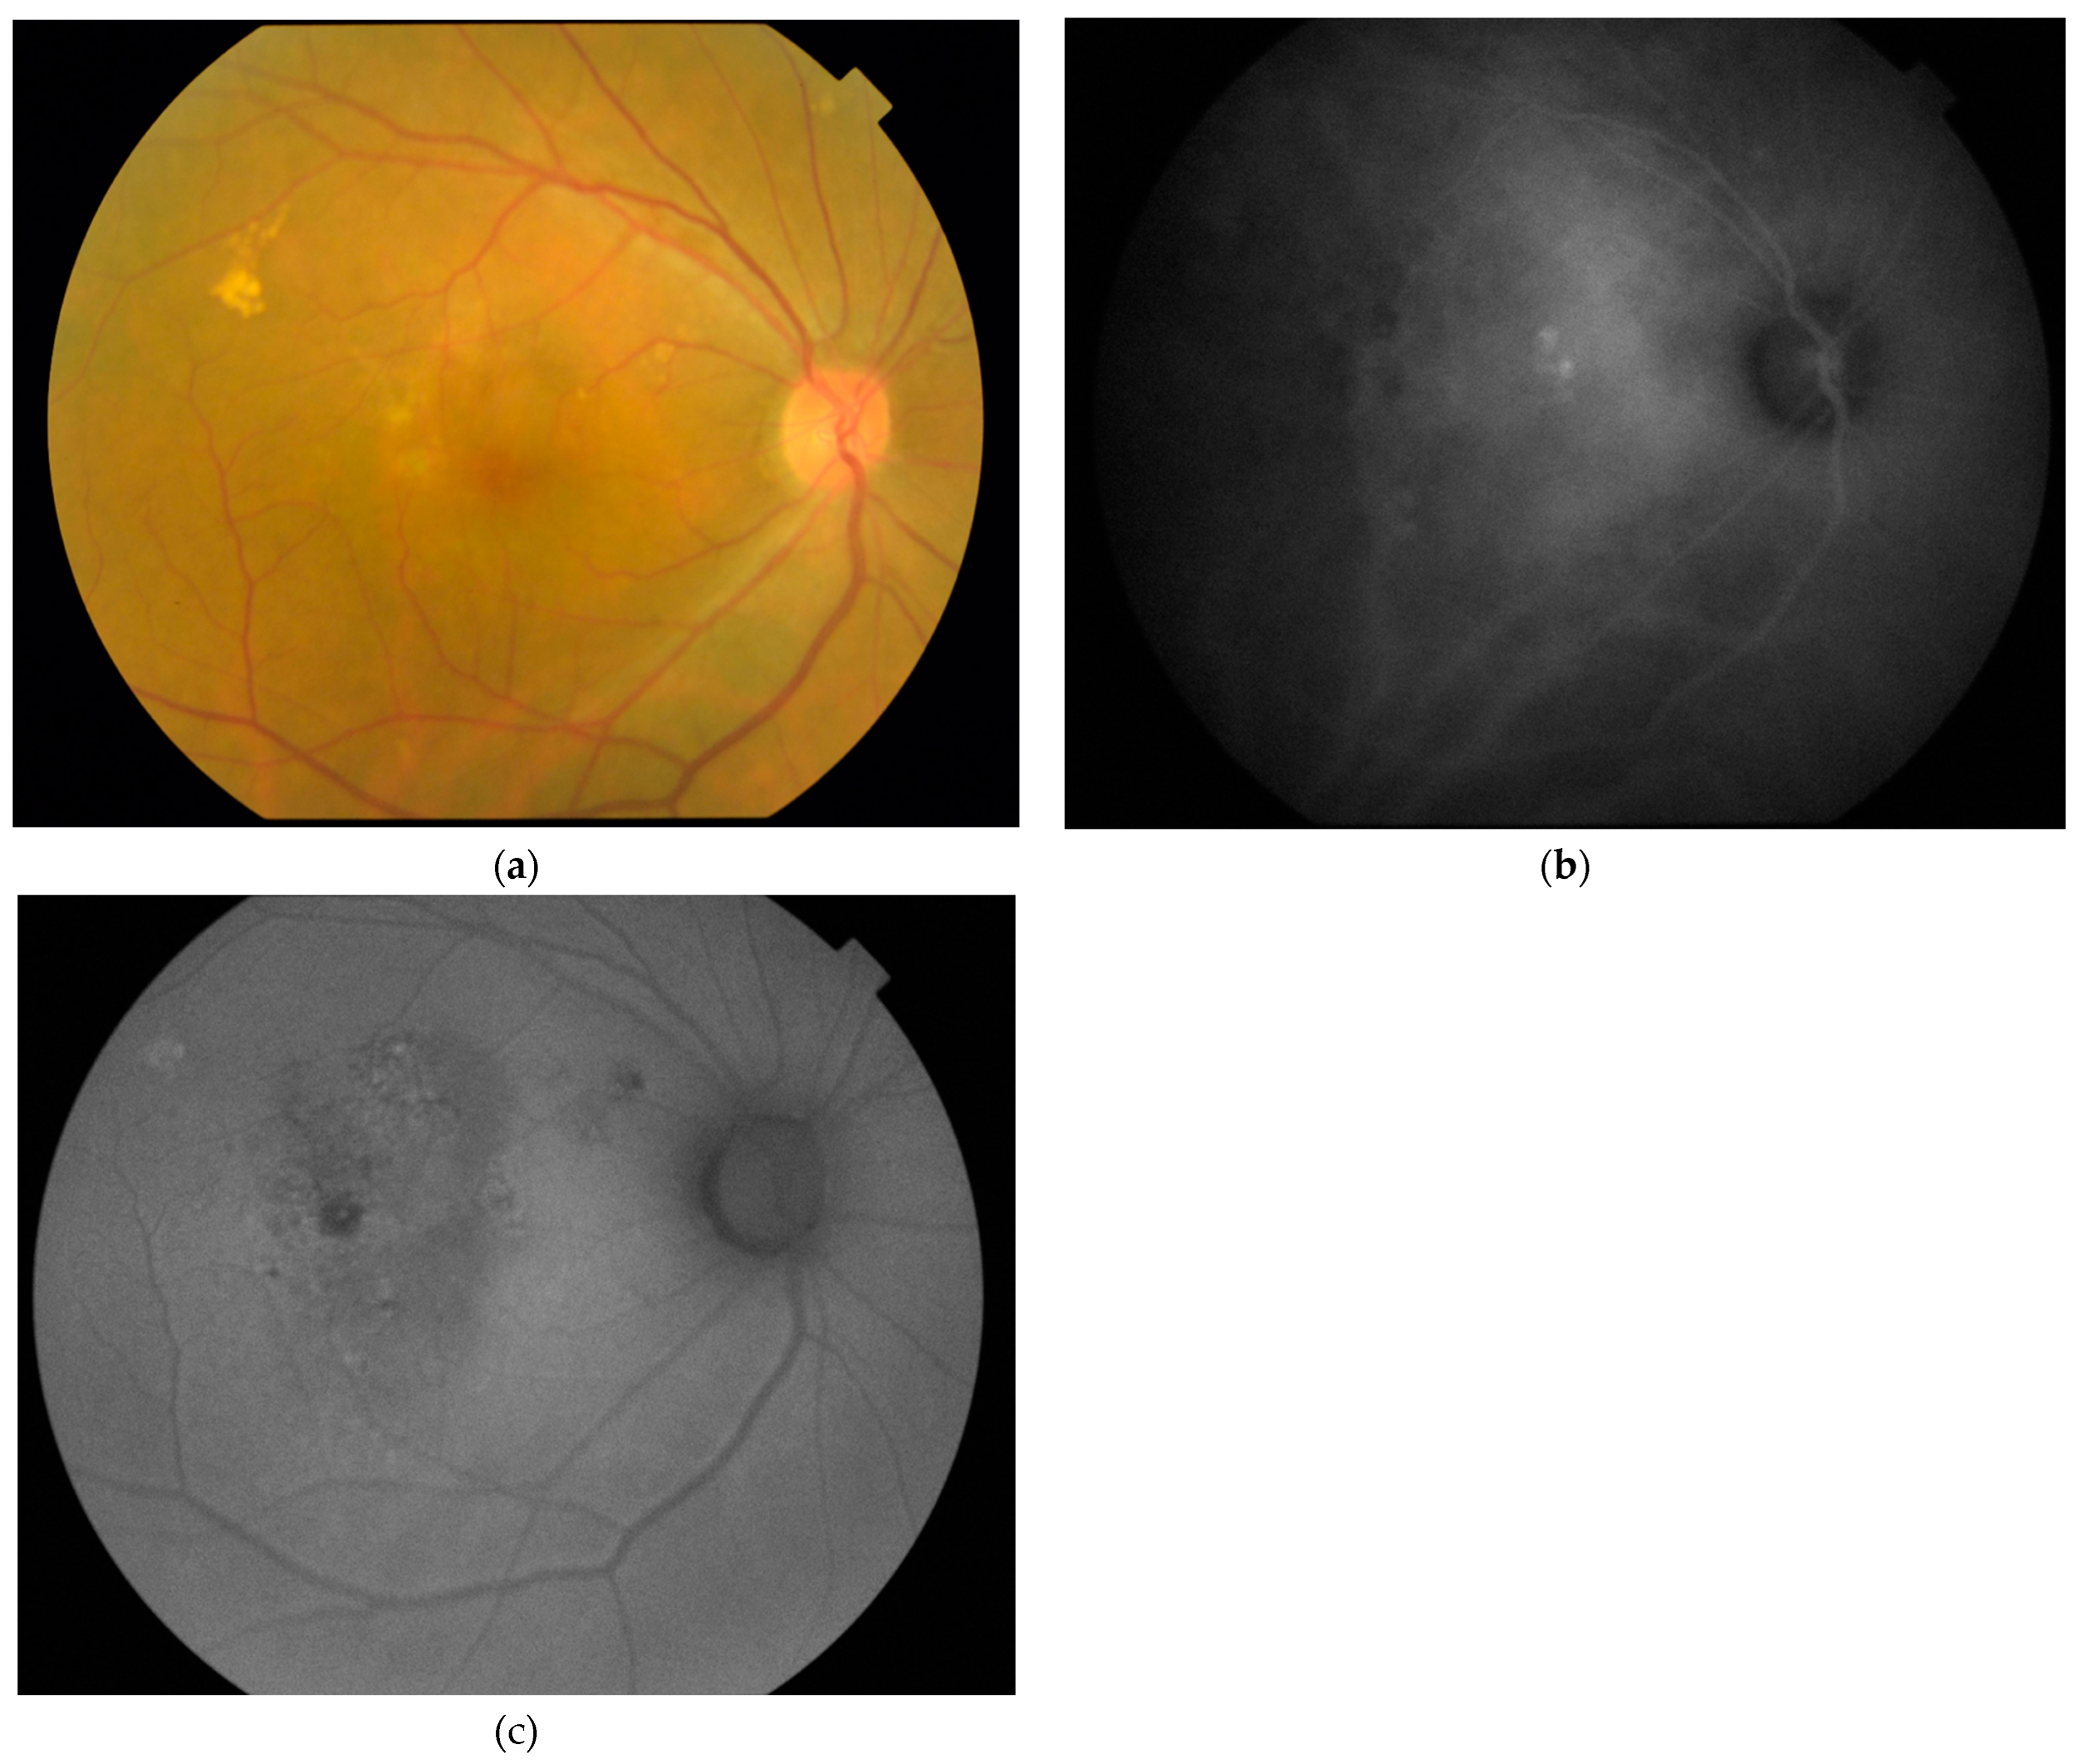

:1. Introduction

2.2. Imaging and Image Analyses